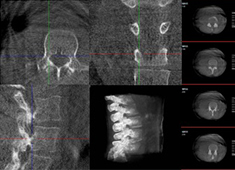

机器人做胸椎手术怎么样:经皮钉棒系统内固定术案例分享

使用骨科手术机器人做胸椎手术的效果怎么样?今天普爱医疗分享一则临床案例——经皮钉棒系统内固定术,看看普爱手术机器人如何助力手术顺利进行。...